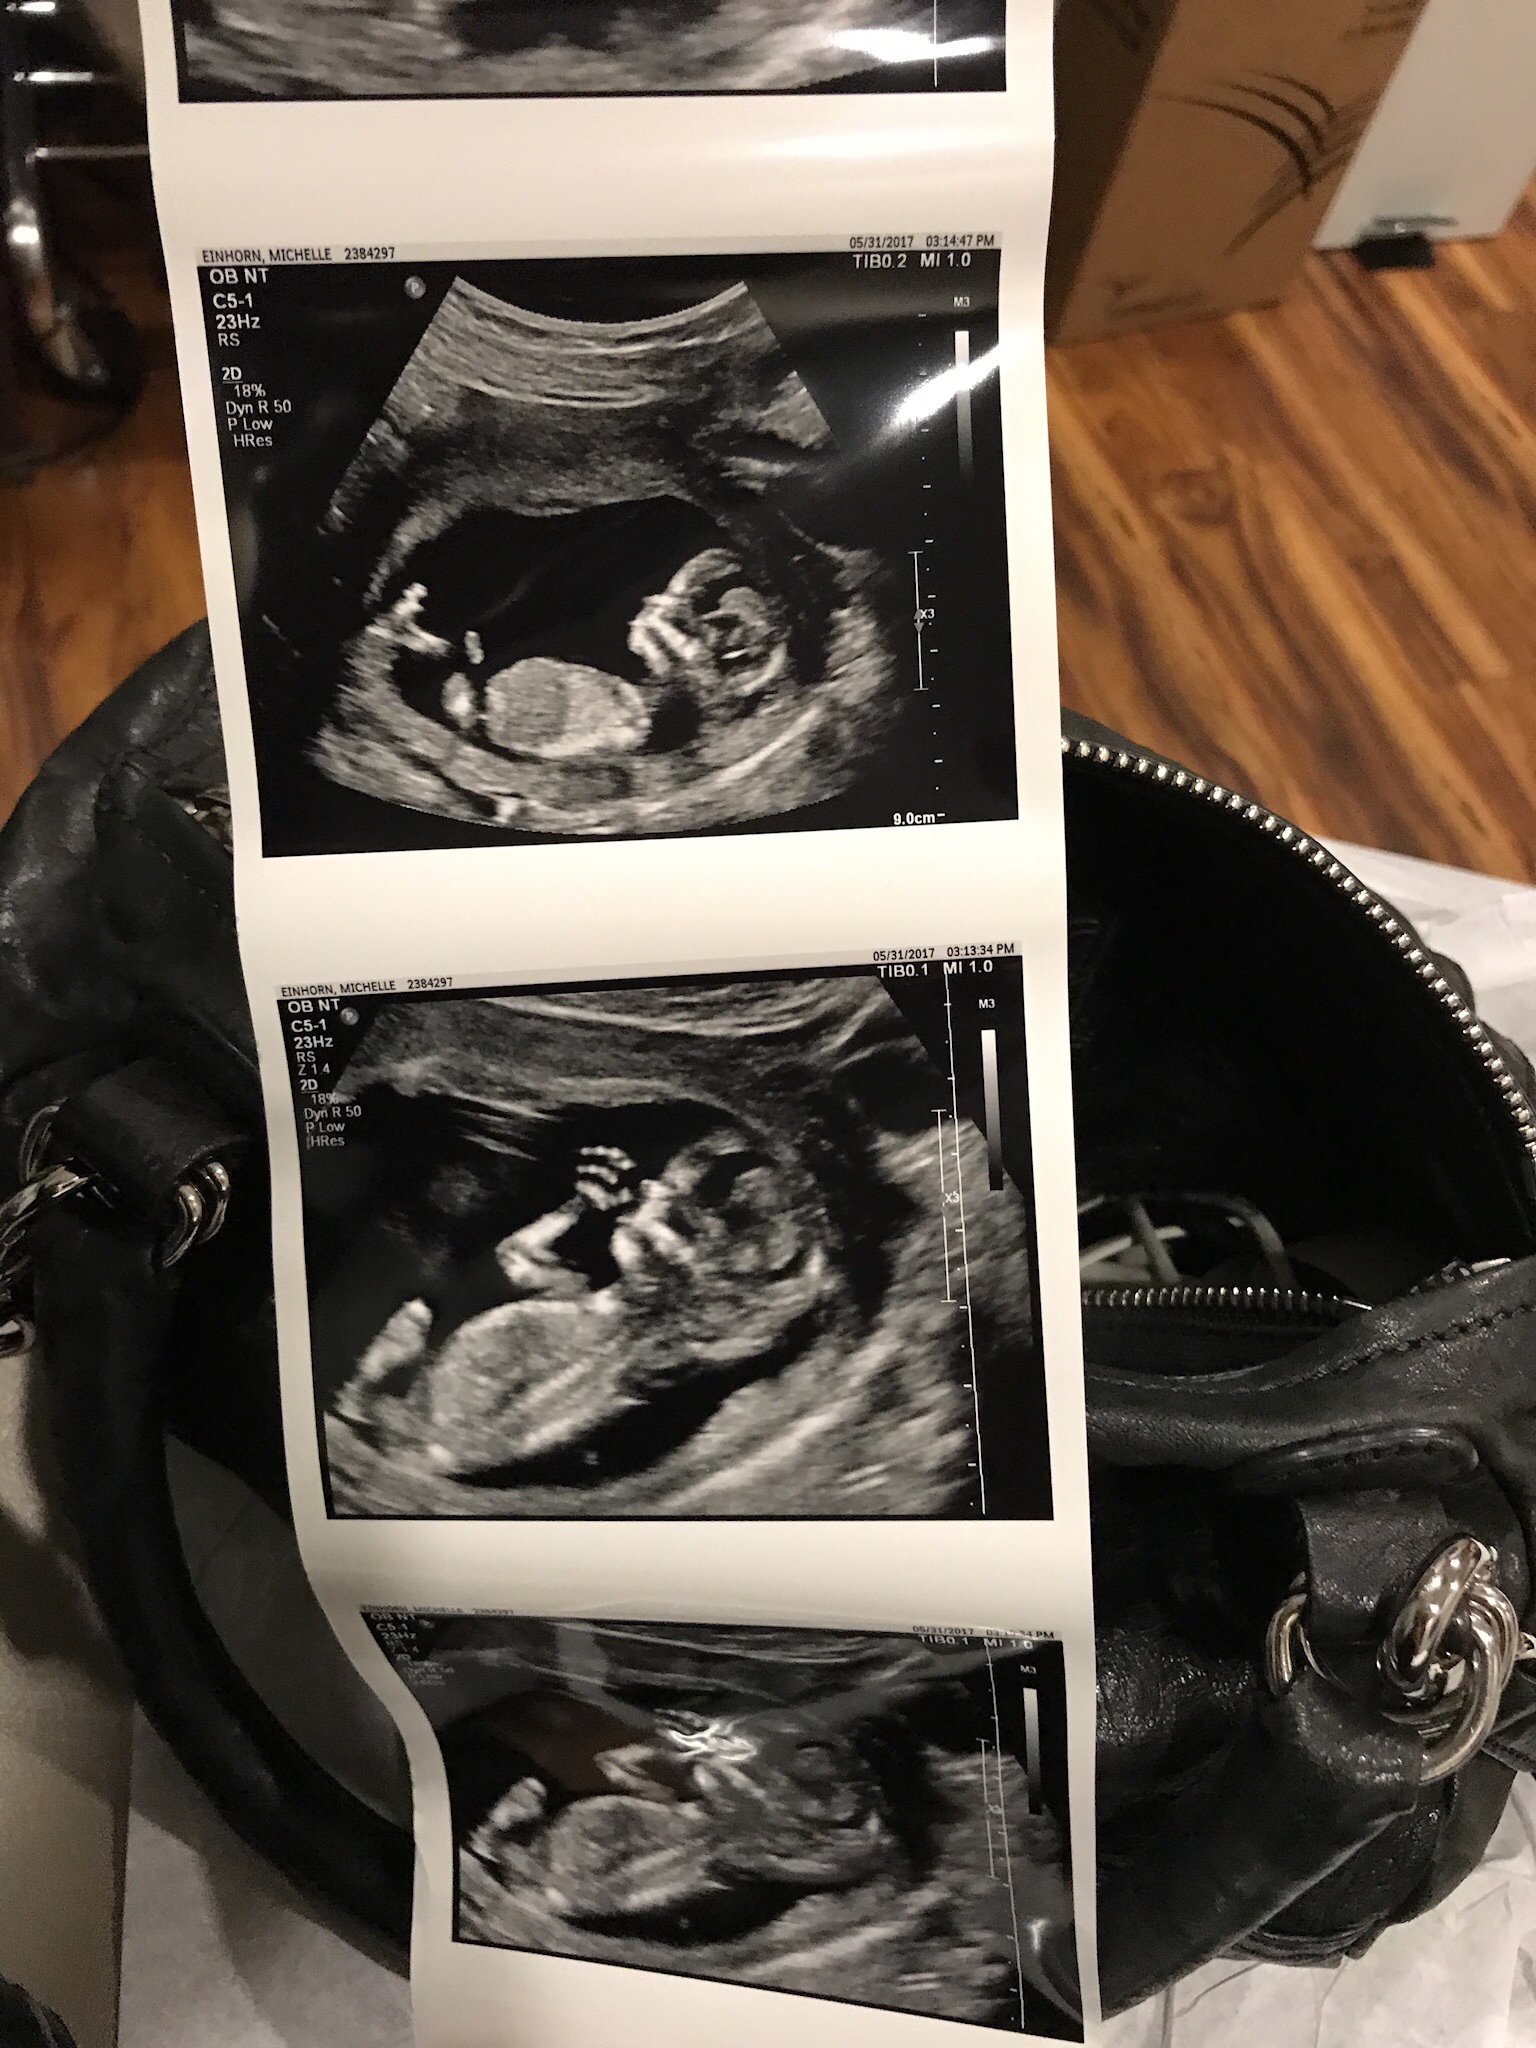

Hi! 13 1/2 weeks and looking for gender guess. I have two boys! There was no visible penis

https://uploads.tapatalk-cdn.com/201...4a4ae82ff8.jpghttps://uploads.tapatalk-cdn.com/201...f3f3c1e899.jpg